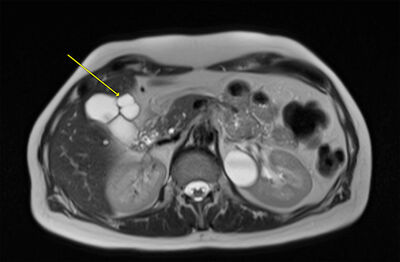

Ómskoðun sýndi belgmein eða blöðrulíkar breytingar miðlægt við gallblöðru sem höfðu einfalt útlit en uppruni þeirra var óljós. Ekki sáust gallsteinar í gallblöðru eða merki um gallblöðrubólgu. Í framhaldi var fengin segulómun af gall- og brisrás (magnetic resonance cholangiopancreatography, MRCP) og sást að um væri að ræða 2 cm stóra vökvafyllta, þunnveggja blöðru með þunnum hálsi inn að gallblöðru, það er að segja, tengsl voru við gallblöðru. Engin víkkun var á gallgöngum. Talið var að umræddar breytingar hefðu útlit sem samrýmdist helst gallblöðrusarpi (Mynd 1). Í uppvinnslu var einnig gerð magaspeglun sem var ómarkverð.

Mynd 1. Segulómun af gall- og brisrás (MRCP) sem sýnir vökvafyllta blöðru (ör) miðlægt við gallblöðru.